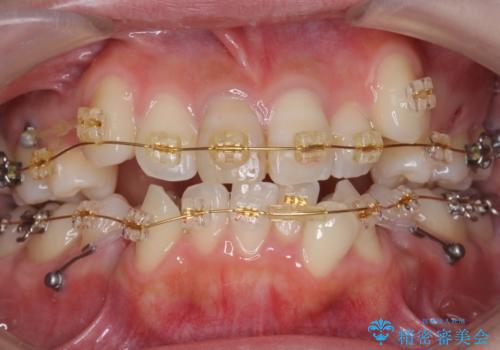

- 審美装置

- 2年

- 10-30回

犬歯のコントロールが難しく、矯正用ミニスクリューを併用しました。

奥歯の歯の間が狭く、ミニスクリューを入れるのも難しい症例でした。